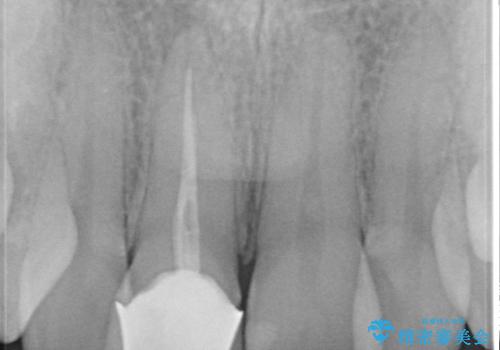

前歯の治療。再根管治療~セラミッククラウン